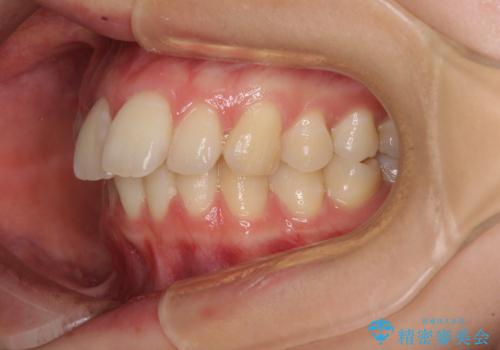

- 前歯の突出感を気にして来院された患者様です。

左右ともに奥歯の咬み合わせが上顎前突となっており、上顎前歯が飛び出している状態でした。

奥歯の咬み合わせ改善が必要であるため、マウスピース矯正より確実に達成のできるワイヤー矯正にて治療を行うこととしました。

奥歯の咬み合わせはしっかりと改善され、前歯の突出感も改善されました。